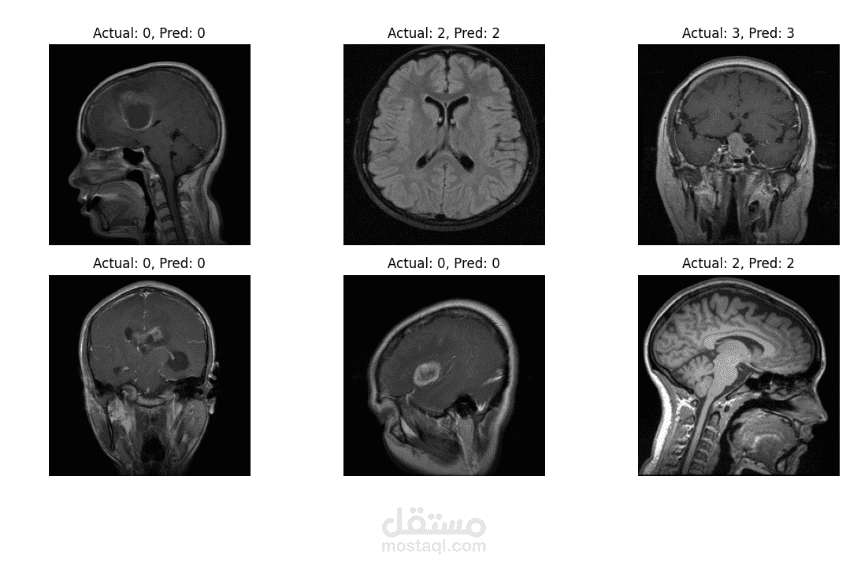

مشروع Brain Tumor Classification هو نظام ذكي يعتمد على تقنيات الذكاء الاصطناعي والتعلم العميق (Deep Learning) لتحليل صور الأشعة الطبية، خاصة صور الرنين المغناطيسي (MRI)، بهدف اكتشاف وتصنيف أورام الدماغ بدقة وسرعة. يساعد هذا النظام الأطباء في التشخيص المبكر واتخاذ قرارات علاجية أكثر دقة.

يقوم النموذج بتحليل صور الدماغ واكتشاف الأنماط غير الطبيعية التي تشير إلى وجود ورم، ثم تصنيف نوع الورم اعتمادًا على خصائصه البصرية.

يتم تدريب النموذج باستخدام مجموعة من صور MRI المصنفة مسبقًا، مما يسمح له بتعلم الفروقات بين الأنسجة الطبيعية وأنواع الأورام المختلفة.

أنواع الأورام التي يمكن تصنيفها

الورم الدبقي (Glioma)

الورم السحائي (Meningioma)

ورم الغدة النخامية (Pituitary Tumor)

دماغ طبيعي (No Tumor)

تصنيف الورم

استخدام نموذج CNN لتحديد نوع الورم.

إظهار نوع الورم ونسبة الثقة في التنبؤ.